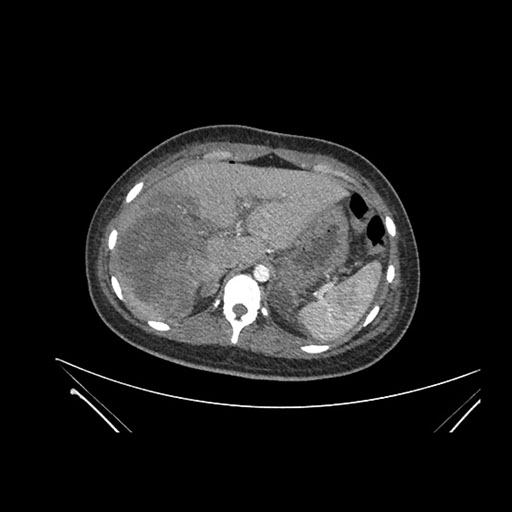

Axial Arterial

Axial Venous

Imaging analysis

Based on initial findings, which issue(s) would you be most concerned about?